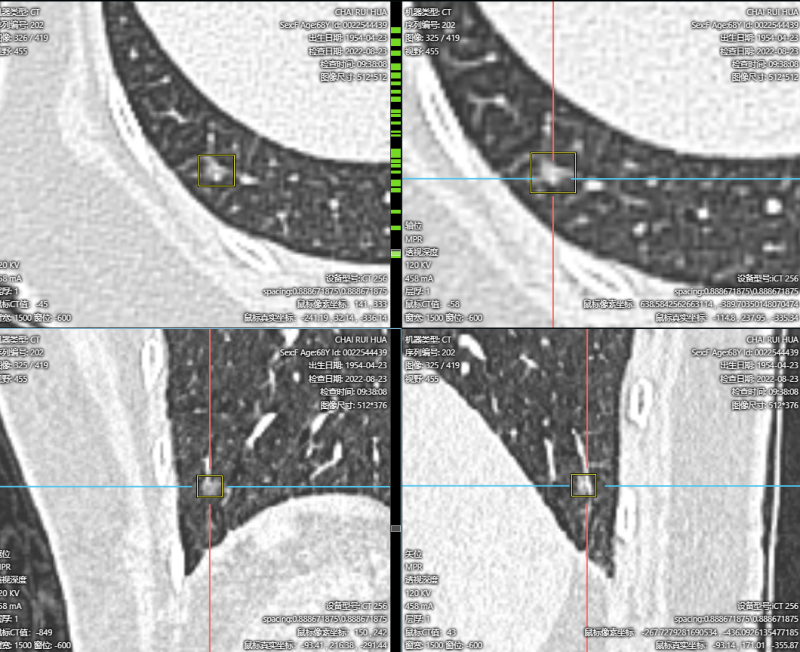

这个结节诊断还是有难度的↓

结节2

诊断:这个结节是一个混杂密度结节,大部分以实性成分为主,周边可见毛刺及分析,由于病灶非常小,如果首次发现还是要小心,但是通过以下多次的随访和复查,我们考虑良性纤维灶的概率更高。

但是由于这个结节位于外周带,非常容易切除,因为和主病灶是同侧,所以这个结节,我么可以考虑一次处理掉。